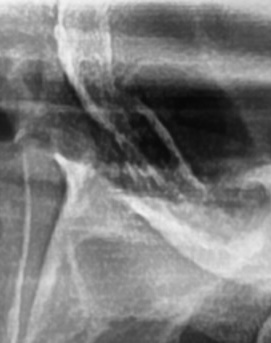

어금니 뒤 잇몸 부음의 문제는 사랑니가 원인이 되는 경우도 많은데 사랑니는 특히 현대인들의 경우 제대로 나오지 못하고 매복되는 경우가 많으며 완전히 나오지 않은 사랑니는 잇몸 속에서 자라면서 주변 잇몸을 자극할 수 있고, 일부만 노출되면 음식물이 끼면서 염증이 생기기도 하며 특히 어금니 뒤쪽 잇몸이 붓고 지속적으로 불편함을 느낀다면 사랑니로 인한 염증을 의심해 볼 수 있어요. 사랑니로 인한 문제의 경우 단순한 소염제나 구강 세정제로 해결되지 않고, 사랑니를 발치해야 잇몸 염증이 해결되는 경우가 많이 있어요

결론적으로는 통증이 심하거나 염증이 오래 지속되는 경우에는 치과를 방문해서 정확한 진단을 받는 것이 중요한데 단순한 잇몸 염증이라면 치석 제거와 항생제 치료로 호전될 수 있지만, 치주염이 진행된 경우라면 보다 적극적인 치료가 필요할 수 있어요. 만약 사랑니로 인해 잇몸이 자꾸 붓는다면 사랑니 발치를 고려해야 하겠고 사랑니가 완전히 매복되어 있다면 수술적인 방법으로 제거해야 할 수도 있어요. 특히 반복적으로 붓는다면 사랑니 검사를 받아보거나, 치과에서 정밀 검진을 통해 치주 상태를 확인하는 것이 필요하다는 점에서 어금니 근처의 잇몸이 반복적으로 불편하다면 꼭 치과를 찾아보시길 바라고 있어요